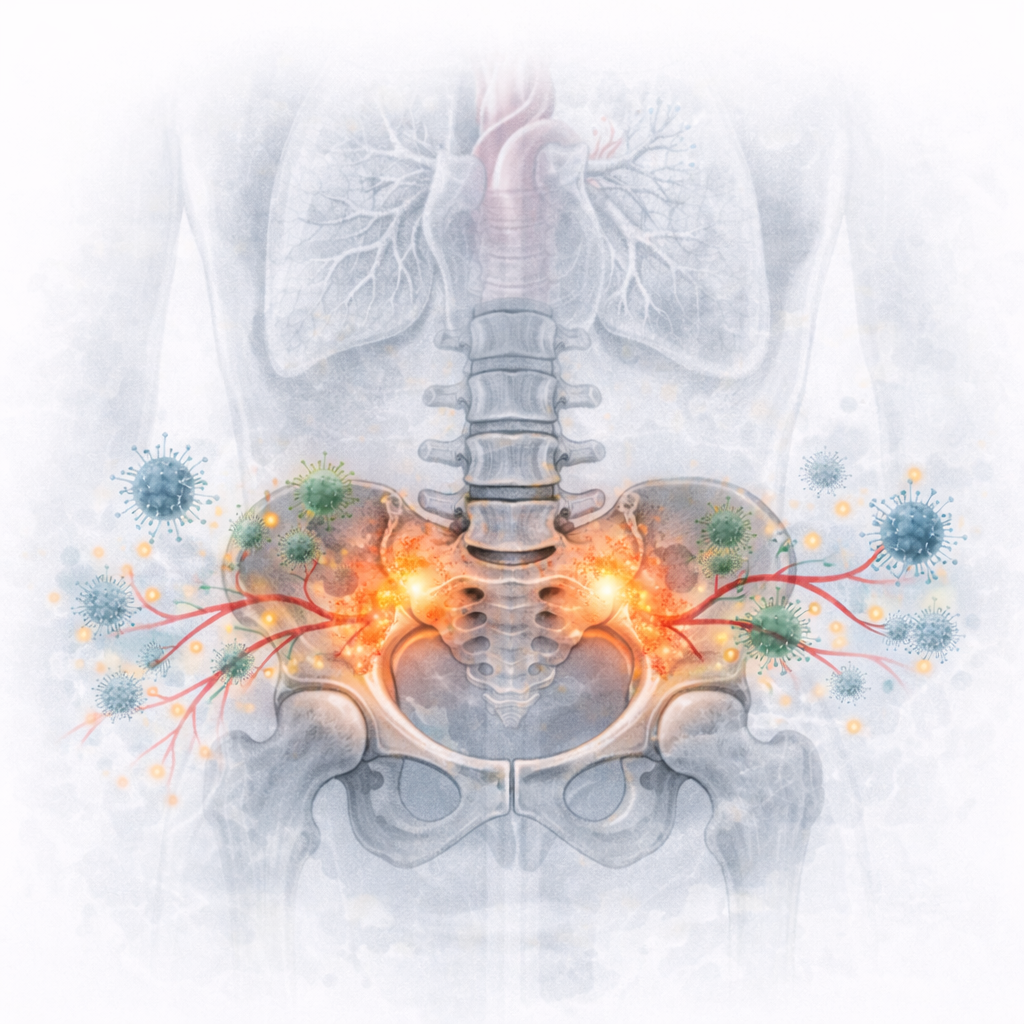

Hoewel minder frequent, moeten inflammatoire en systemische aandoeningen altijd worden uitgesloten bij passende kliniek.

Te overwegen:

Axiale spondyloartritis

Infectieuze spondylodiscitis

Maligniteit of metastasen

Metabole botziekten

Met name nachtelijke pijn, ochtendstijfheid en systemische symptomen verdienen extra aandacht.